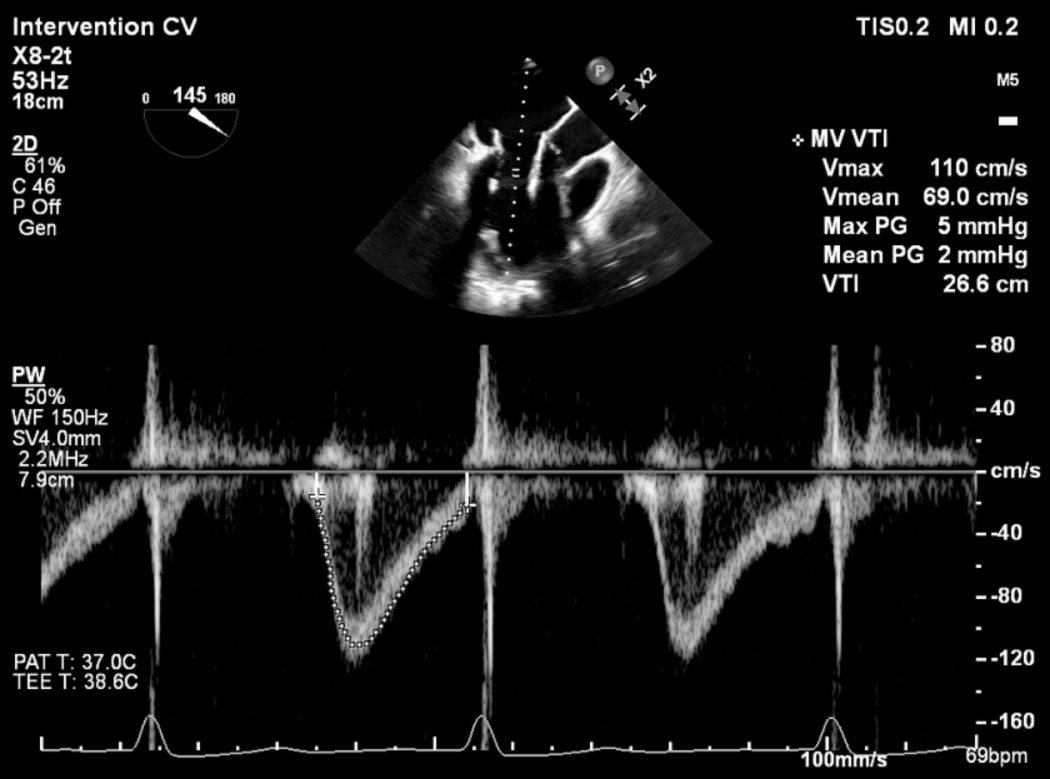

手术采用左侧第五肋间微创切口入路,超声引导下经心尖将导丝置入左房,送入瓣膜输送系统,经过一系列超声定位后逐渐释放瓣膜。确认瓣膜位置满意后撤出输送系统,瓣架恢复膨胀完全、锚定良好,人工二尖瓣瓣叶形态完好,无反流及无瓣周漏,人工二尖瓣峰值流速1.10m/s、平均压差2mmHg,峰值压差5mmHg,由连续多普勒据PHT估测面积约3.5cm²,左室流出道无梗阻,峰值流速0.76m/s。术中出血约100ml,无输血,术后患者安全返回监护室。

血流动力学